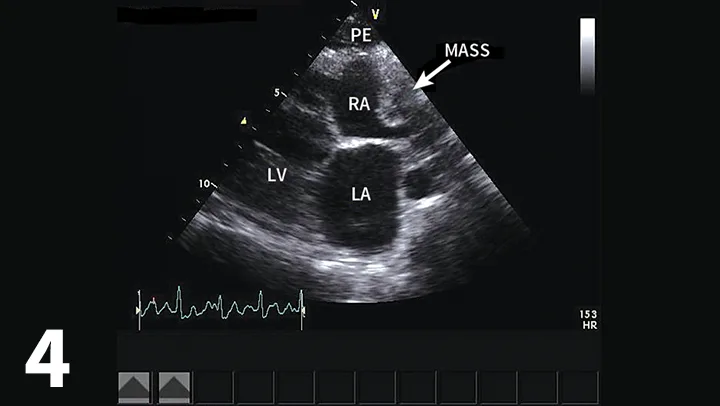

• Right atrial masses are most typically hemangiosarcoma (Figure 4).7

Featured Image

Figure 4

Right parasternal long-axis echocardiographic view of a dog with a small accumulation of pericardial effusion and an infiltrative right atrial mass (hemangiosarcoma most likely). (PE = pericardial effusion, RA = right atrium, LA = left atrium, LV = left ventricle)